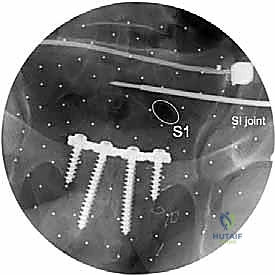

يتم الاستعانة بجهاز الأشعة السينية المتحرك داخل غرفة العمليات (C-arm Fluoroscopy) للتأكد من وضعية المسامير بدقة المليمتر، لضمان عدم اختراقها للأعصاب أو الأوعية الدموية.